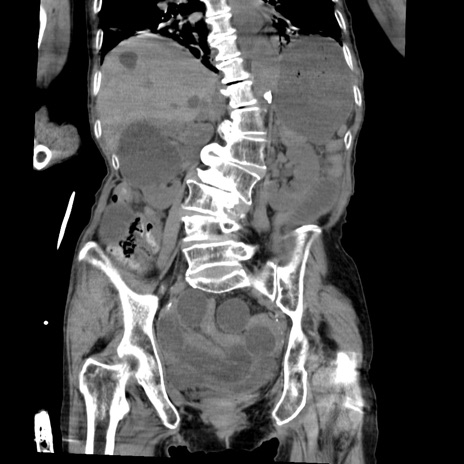

症例27(冠状断像)

【症例】80歳代女性

【主訴】嘔吐、腹痛

【現病歴】数時間前より嘔吐あり。心窩部痛出現し、徐々に右下腹痛あり。その後も数回嘔吐あり救急搬送となる。

【既往歴】左大腿骨頚部骨折手術

【身体所見】腹部は膨隆しているが軟らかく圧痛なし。腸雑音はやや亢進。

【データ】WBC 12000、CRP 19.05